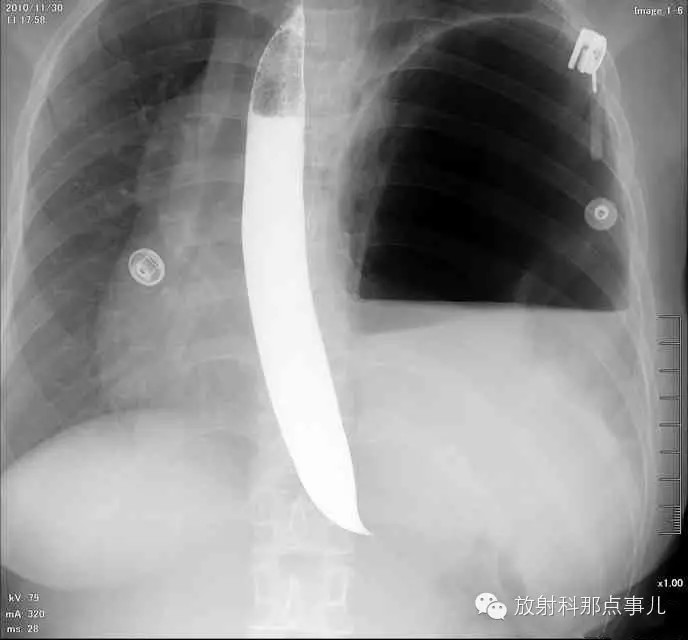

【病例学习】膈疝一例X线诊断

24岁,女性,腹痛渐加重并呕吐。

患者系顺产后18天产妇,产后感觉腹部疼痛不适,自认为正常反应,近两日因胸闷、腹部疼痛加剧伴呕吐来院就诊。

门诊腹部透视发现左侧胸腔巨大气液平面,为排除膈疝口服钡剂,但造影剂未见进入胃内。嘱住院,外科给予胃肠减压、补液等处理常规处理(未引流出明显气、液体)。5个半小时后再次检查,见少量造影剂进入消化道;为进一步了解情况,予泛影葡胺分别经胃管推注及口服,但均未进入胃内。当天进行外科急诊手术。

大部分胃、脾及横结肠均经过胸肋三角疝入左侧胸腔内,并见疝环形成。